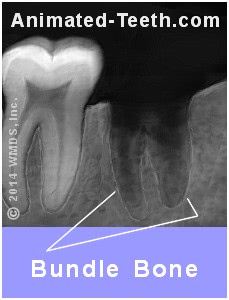

X-ray showing tooth socket bundle bone.

Immediately subsequently an extraction, the outline of the socket is easily seen.

FYI: Bundle Bone

If your dentist would take an 10-ray immediately subsequently pulling your tooth, it would bear witness a white line outlining the shape of your tooth'due south socket (see our graphic).

This is termed "bundle os" and it'southward the layer of bone in which the fibers that anchored your tooth in place (its periodontal ligament) were embedded.

Since the tooth is now gone and this outline of bone no longer has a office, as the healing procedure progresses and new bone is formed, this layer will be gradually resorbed (be broken down and dispersed past your body).

Afterwards near 18 months or so, information technology volition accept totally disappeared and the outline of the socket volition have been mostly lost.